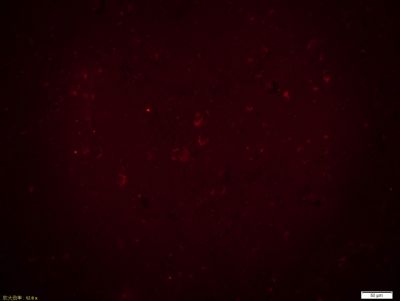

| 产品图片 | ![]() Sample: Lung (Mouse) Lysate at 40 ug Primary: Anti-RAB7 (bs-6703R) at 1/300 dilution Secondary: IRDye800CW Goat Anti-Rabbit IgG at 1/20000 dilution Predicted band size: 23 kD Observed band size: 18 kD ![]() Paraformaldehyde-fixed, paraffin embedded (Human brain glioma); Antigen retrieval by boiling in sodium citrate buffer (pH6.0) for 15min; Block endogenous peroxidase by 3% hydrogen peroxide for 20 minutes; Blocking buffer (normal goat serum) at 37°C for 30min; Antibody incubation with (RAB7) Polyclonal Antibody, Unconjugated (bs-6703R) at 1:400 overnight at 4°C, followed by operating according to SP Kit(Rabbit) (sp-0023) instructionsand DAB staining. ![]() Paraformaldehyde-fixed, paraffin embedded (Human brain glioma); Antigen retrieval by boiling in sodium citrate buffer (pH6.0) for 15min; Block endogenous peroxidase by 3% hydrogen peroxide for 20 minutes; Blocking buffer (normal goat serum) at 37°C for 30min; Incubation: Anti-RAB7 Antibody, conjugated (bs-6703R-AF594) at 1:100 overnight at 4°C; DAPI (5ug/ml, blue, C-0033) was used to stain the cell nuclei. ![]() Blank control: A431. Primary Antibody (green line): Rabbit Anti-RAB7 antibody (bs-6703R) Dilution: 1μg /10^6 cells; Isotype Control Antibody (orange line): Rabbit IgG . Secondary Antibody: Goat anti-rabbit IgG-AF647 Dilution: 1μg /test. Protocol The cells were fixed with 4% PFA (10min at room temperature)and then permeabilized with 20% PBST for 20 min at room temperature. The cells were then incubated in 5%BSA to block non-specific protein-protein interactions for 30 min at -20℃ .Cells stained with Primary Antibody for 30 min at room temperature. The secondary antibody used for 40 min at room temperature. Acquisition of 20,000 events was performed. |